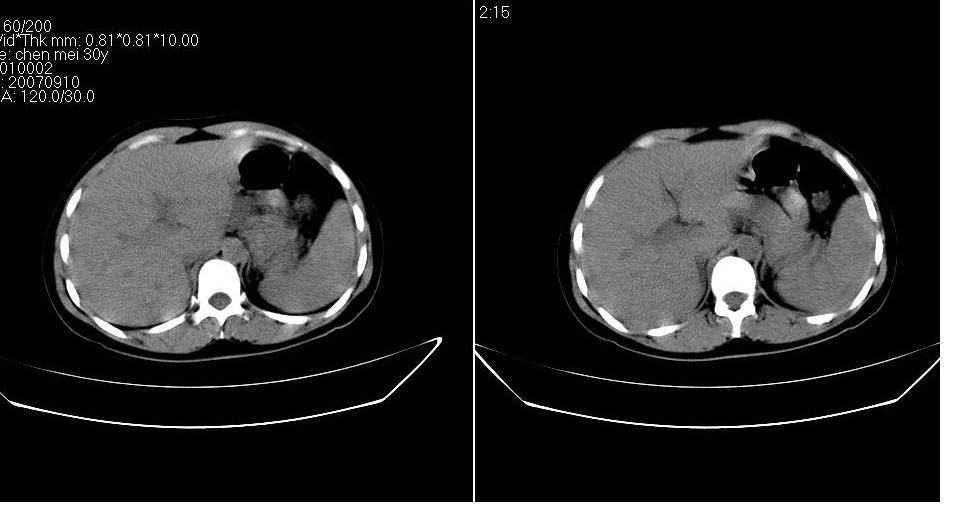

以下是引用求知若渴在2007-9-10 20:08:00的发言:[br]病变以脂肪成分为主,应该是错构瘤。另肝内胆管结石

以下是引用xulianj在2007-9-10 20:51:00的发言:[br]错构瘤,支持。含脂肪成分较多,证明较为成熟。

以下是引用齐原在2007-9-10 20:10:00的发言:[br]病变以脂肪成分为主,应该是错构瘤。另肝内胆管结石

以下是引用王仕学在2007-9-10 21:34:00的发言:[br]有脂肪密度,哪怕是一点点,首先考虑错构瘤。还是增强吧,好说些!